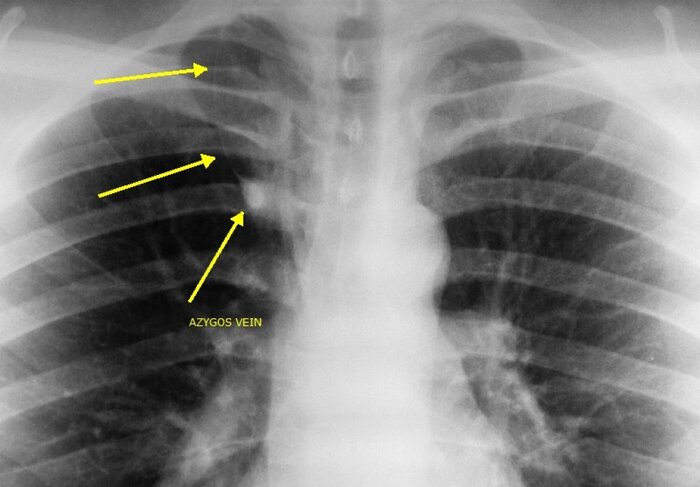

Расшифровка цифровых кодов флюорографии с примерами

04 - Расширение тени средостения, в том числе увеличение размеров корня.

01 - Кольцевидная тень (полость).

02 - Затемнение в легочной ткани (инфильтрация,ателектаз, округлая тень, среднедолевой синдром и др.).

03 - Очаговые тени в легочной ткани.

Примечания:

При сочетании нескольких из перечисленных изменений каждое из них отмечается соответствующим кодом в каждой графоклетке.

Локализация, протяженность изменений отмечается дробью по второй графоклетке 1; 2; 3; 4; в числителе - правое легкое, в знаменателе - левое легкое (по полям).

Номер шифра легочных полей: 1 - первое, 2 - второе, 3 - третье, 4 - первое и второе, 5 - первое и третье, 6 - второе и третье, 7 - первое, второе и третье.